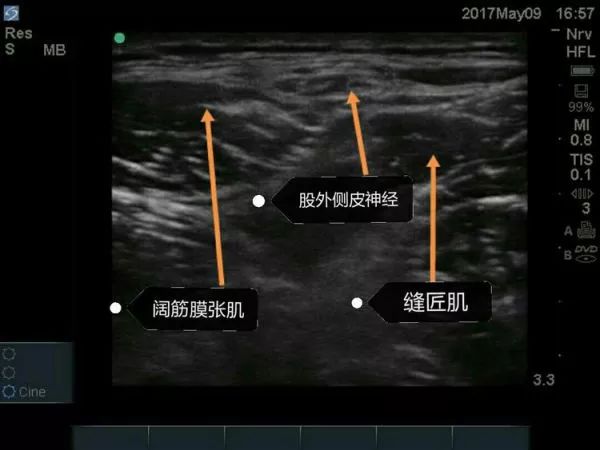

②探头的位置: 横向放置,紧贴髂前上棘的下方,缝匠肌SaM的外侧缘。

③目标: 局麻药在阔筋膜张肌TFL和缝匠肌之间扩展。

④局麻药: 5-10ml。

超声引导下股外侧皮神经阻滞技术为骨科髋关节手术切口提供理想术后镇痛效果。

超声引导下局麻药在股外侧皮神经周围扩散